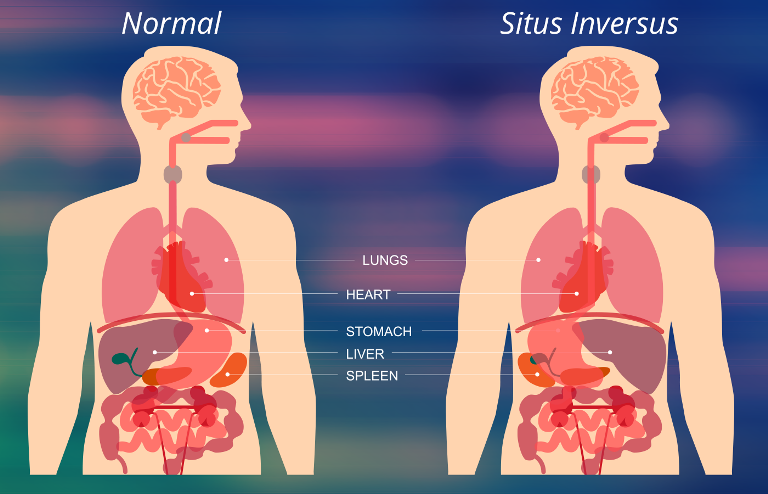

Most of her internal organs were flipped around, a mostly mirrored image of the way the human body should be.

Bentley had situs inversus, a genetic disorder that affects 1 in 10,000 people. She had a rarer type called ‘situs inversus with levocardia’ as she had her heart on the left side of the body while all other organs were flipped around.

One of her lungs only had two lobes instead of three, and her blood vessels developed at odd angles and in odd places.